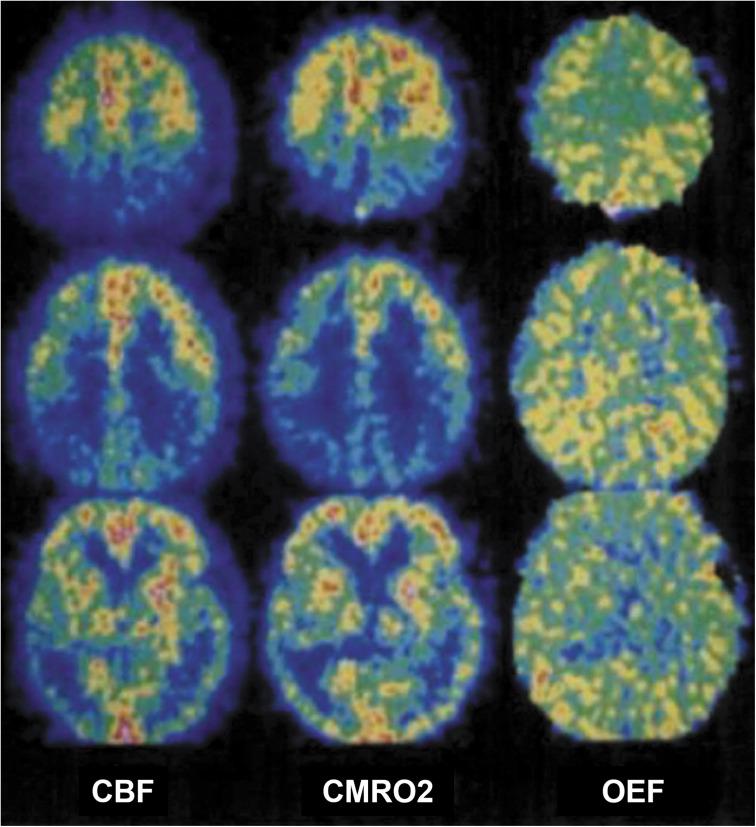

The metabolic rate of oxygen (MRO) is fundamental to tissue metabolism. Determination of MRO demands knowledge of the arterio-venous difference in hemoglobin-bound oxygen concentration, typically expressed as oxygen extraction fraction (OEF), and blood flow rate (BFR). MRI is uniquely suited for measurement of both these quantities, yielding MRO in absolute physiologic units of µmol O min/100 g tissue. Two approaches are discussed, both relying on hemoglobin magnetism. Emphasis will be on cerebral oxygen metabolism expressed in terms of the cerebral MRO (CMRO), but translation of the relevant technologies to other organs, including kidney and placenta will be touched upon as well. The first class of methods exploits the blood's bulk magnetic susceptibility, which can be derived from field maps. The second is based on measurement of blood water T, which is modulated by diffusion and exchange in the local-induced fields within and surrounding erythrocytes. Some whole-organ methods achieve temporal resolution adequate to permit time-series studies of brain energetics, for instance, during sleep in the scanner with concurrent electroencephalogram (EEG) sleep stage monitoring. Conversely, trading temporal for spatial resolution has led to techniques for spatially resolved approaches based on quantitative blood oxygen level dependent (BOLD) or calibrated BOLD models, allowing regional assessment of vascular-metabolic parameters, both also exploiting deoxyhemoglobin paramagnetism like their whole-organ counterparts.

氧代谢率(MRO)是组织代谢的基础。要确定 MRO,需要了解血红蛋白结合氧浓度的动静脉差异,通常以氧提取分数(OEF)和血流速率(BFR)表示。MRI 非常适合测量这两个量,以绝对生理单位(每 100 克组织 100 微摩尔氧/分钟)测量 MRO。本文讨论了两种方法,都依赖于血红蛋白的磁性。重点将放在以脑 MRO(CMRO)表示的脑氧代谢上,但也将涉及将相关技术转化为其他器官,包括肾脏和胎盘。第一类方法利用血液的整体磁化率,可以从磁场图中得出。第二种方法基于测量血液水 T1,这受红细胞内和周围局部诱导场中的扩散和交换调制。一些整体器官方法可以实现足够的时间分辨率,以允许在扫描器中进行脑能量学的时间序列研究,例如在脑电图(EEG)睡眠阶段监测的同时进行睡眠。相反,为了提高空间分辨率,已经开发出了基于定量血氧水平依赖(BOLD)或校准 BOLD 模型的空间分辨率方法,允许对血管代谢参数进行区域评估,这些方法也像它们的整体器官对应物一样利用去氧血红蛋白的顺磁性。